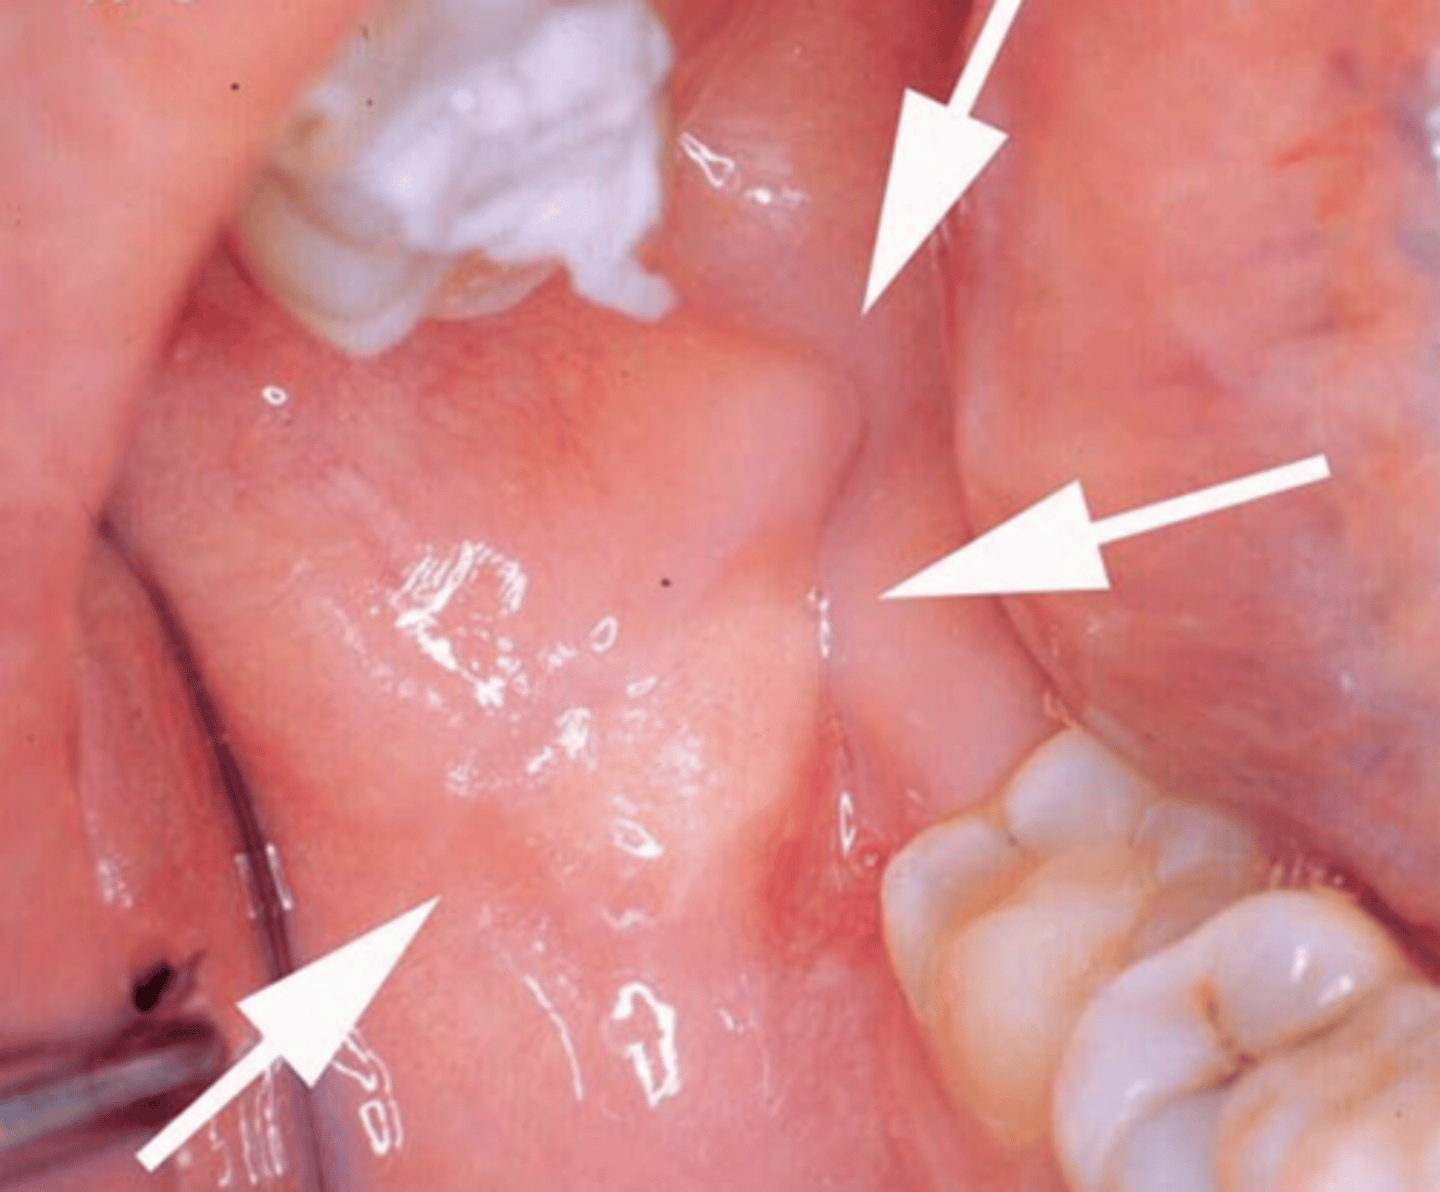

describe how a granular cell tumor would look/feel clinically:

yellowish, raised, firm to palpation, non-ulcerated lesion

this is painless

where is the most common site in the oral cavity for a granular cell tumor?

tongue